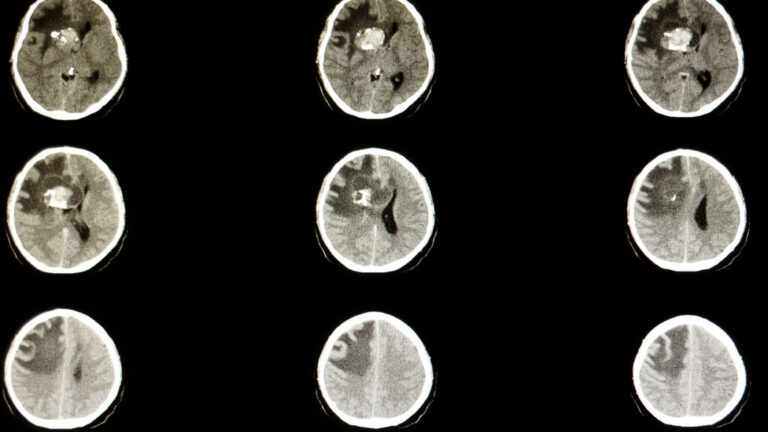

The deal’s centerpiece is Day One’s Ojemda, which won U.S. approval in 2024 as a treatment for pediatric low-grade glioma, the most common form of childhood brain cancer. Servier also said the deal would expand its pipeline of experimental medicines for rare cancers.